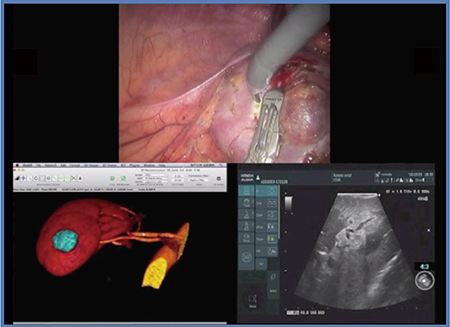

症例1は,36歳,男性,右腎細胞がんで,RENAL Nephrometry Score(RNS)は7aである(図2)。腫瘍はやや埋没しており,経腹膜アプローチにてRAPNを施行した。術中エコーを用いて全周のマーキングを丹念に行っていくが,L51Kはケーブルが柔らかく,腫瘍に押し当てながら走査しても把持鉗子から外れることがないため,把持したままストレスなく操作することができる。本症例は切除断端陰性で,出血は少量,阻血時間は19分であった。

図2 症例1:RNS 7aの右腎細胞がん(36歳,男性)